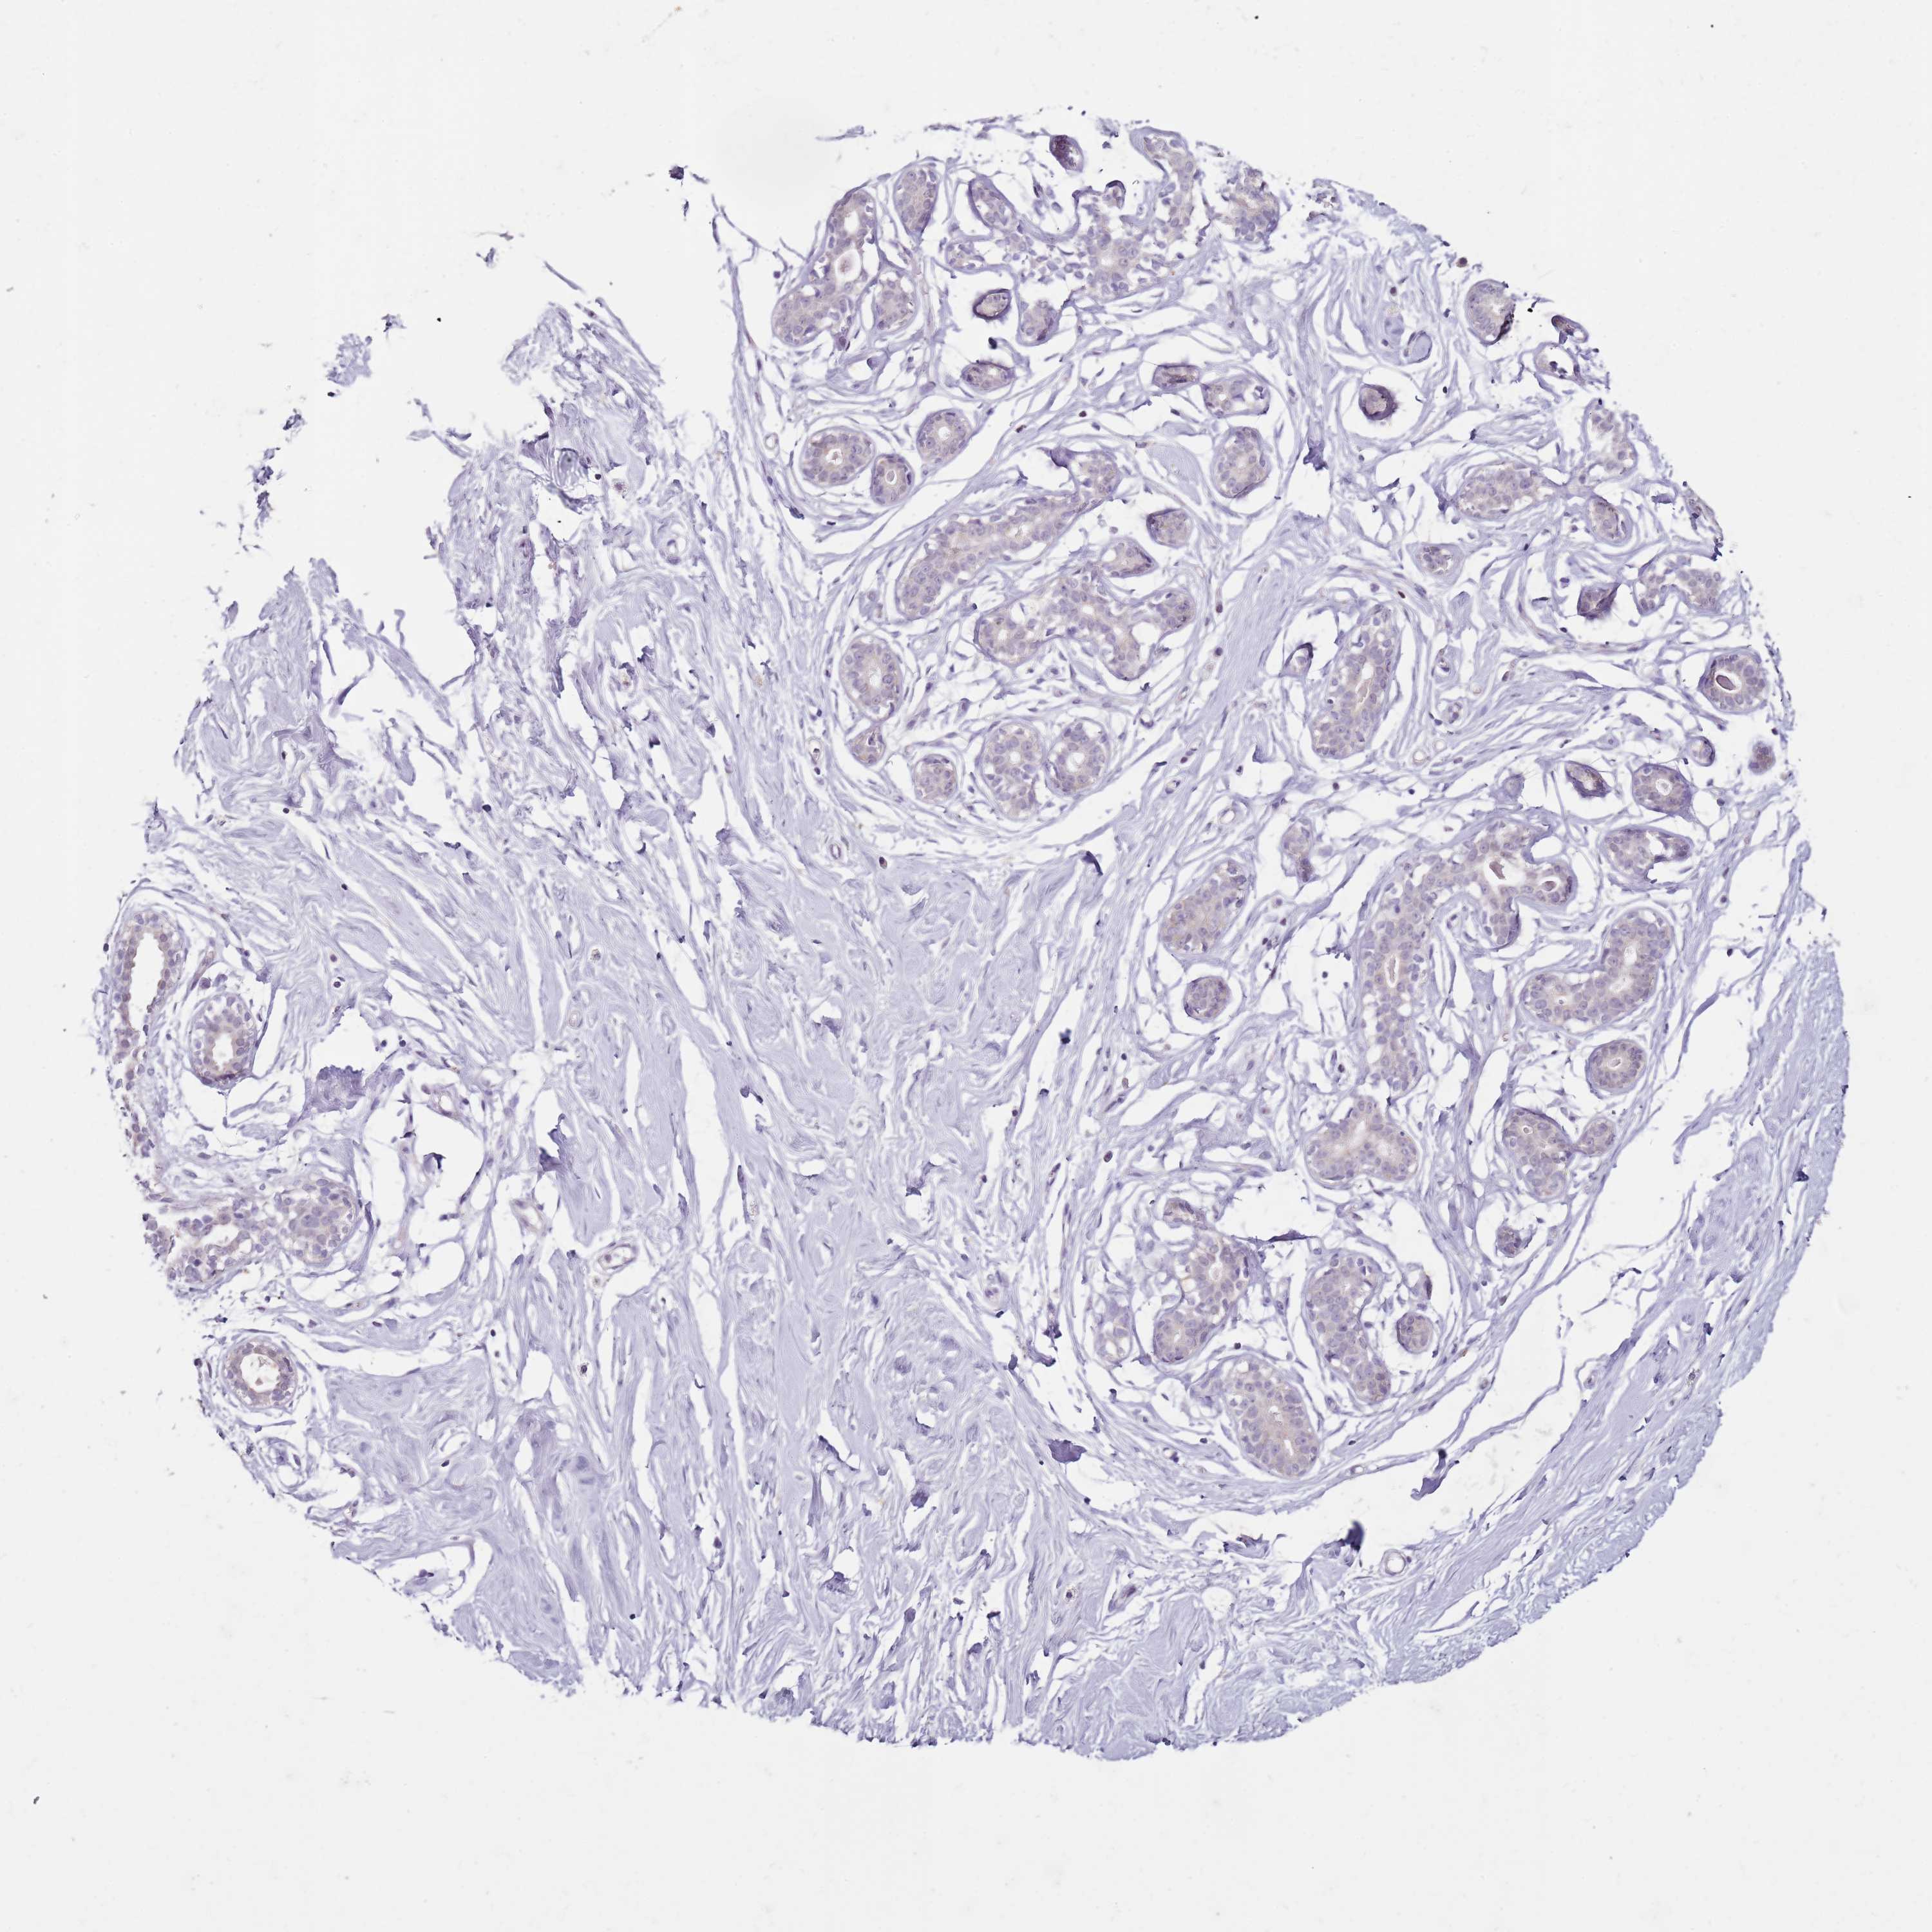

BREAST - Antibody stainingi

Antibody staining in the annotated cell types in the current human tissue is reported as not detected, low, medium, or high, based on conventional immunohistochemistry profiling in selected tissues. This score is based on the combination of the staining intensity and fraction of stained cells.

Each image is clickable and will lead to virtual microscopy that enables deeper exploration of all samples and also displays staining intensity scores, fraction scores and subcellular localization as well as patient and tissue information for each sample.

Antibody HPA027296Antibody HPA054276Antibody CAB047333

Adipocytes Not detectedNot detectedNot detected

Glandular cells Not detectedMediumNot detected

Myoepithelial cells Not detectedMediumNot detected